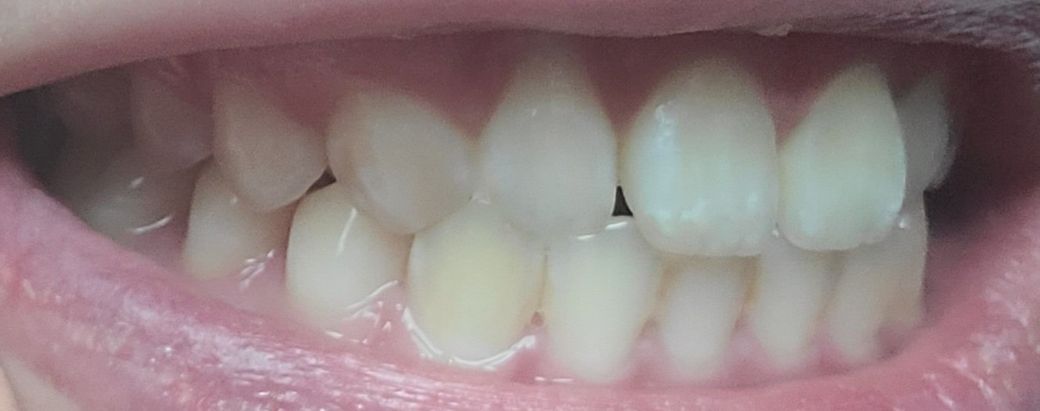

송곳니랑 그부근 어금니가 좀 더 틀어져서 깊게?물려요 턱이 비대칭이있긴한데 이정도비대칭은 사람마다 있다고들 하는데

-한쪽 송곳니은 살짝 떠있고 반대쪽은 잘물려요

왜 그런건지 모르겠어요 중심선이 안 맞아서 그런 건가요?

앞니 옆쪽 치아하나도 위아래가 부딪힙니다